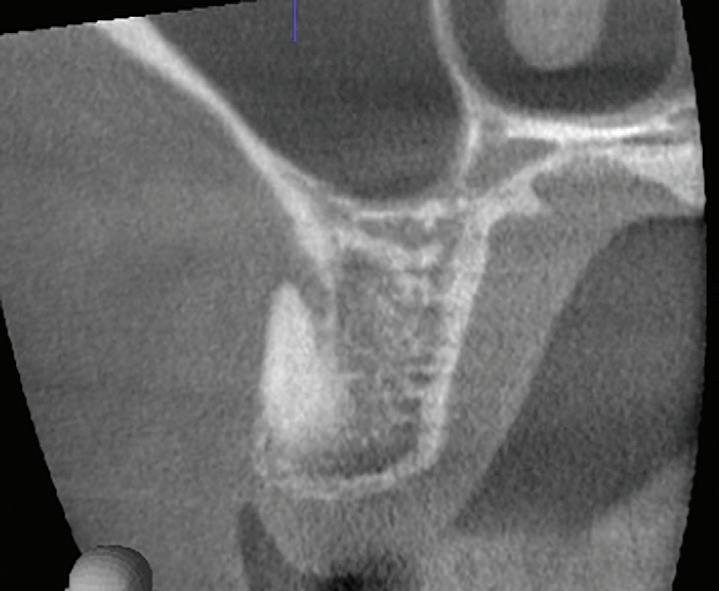

These CAIPP lesions are best identified and monitored with high-resolution CBCT scans (Fig 5). However, even advanced CBCT systems, with voxel sizes as small as 0.075 mm, are not capable of reliably detecting cracks, which are typically much narrower.45 Therefore, the presence of a CAIPP defect, combined with careful clinical diagnostics and evaluation, remains the most reliable indirect indicator of a crack with radicular extension.

The presumed clinical significance of a lingering CAIPP defect is that the persistent biofilm in the crack can lead to further periodontal breakdown and symptoms. However, the changes in these areas were monitored over the course of

previous studies, and these bony lesions did not progress over time and remained asymptomatic.4,26 Together, these studies demonstrated that the persistent bony defect adjacent to the cracks may remain stable and asymptomatic over time, making saving teeth with this technique a realistic option for patients.

Fig 5. CBCT images of a crack-associated isolated periodontal pocketing defect associated with a distal crack in the mandibular right first molar. A. Sagittal view showing angular crestal bone loss (arrow) along a distal radicular crack at the cervical margin. B. CBCT 3-dimensional rendering showing the defect (arrow) at the distal root. C. Axial view showing the defect (arrow) at the distal root.